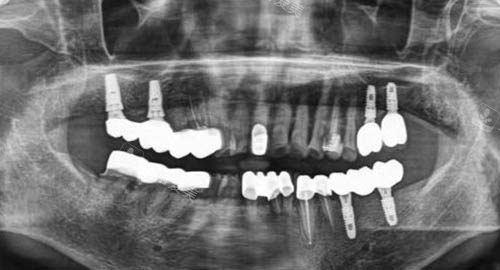

多颗牙齿种植ct

二、医师持证上岗,正规有确保

贝格口腔的医师团队均持证上岗,他们都具备扎实的正规知识和丰富的临床经验。

每一位医生都经过了系统的医学教育和严格的考核,拥有相应的执业资格证书。

无论是常见的牙齿清洁、补牙,还是复杂的牙齿矫正、种植牙手术等,这些正规的医师都能够凭借自己的正规技能为患者提供优质的诊疗方案。